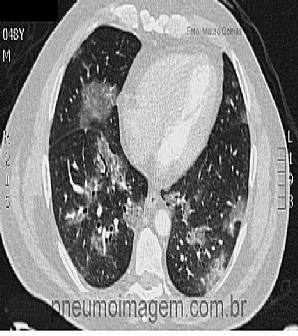

Veja imagens de pneumonia por Influenza no PneumoImagem, clique aqui.